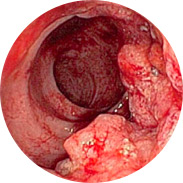

A végbél nyálkahártyájának gyulladása és felfúvódása

A vérzés vérszegénységhez vezethet

A testhőmérséklet emelkedése súlyos gyulladás mellett lázhoz vezethet

És a legrosszabb a végbélrák!A Hemoren nagyszabású klinikai vizsgálatait 2016-ban végezték el a Magyar Orvosi Központban (Budapest). Összesen több mint 1000, különböző stádiumú aranyértől szenvedő férfi és nő vett részt a vizsgálatokban. Valamennyi alany Hemoren krémet használt 3 hétig. A vizsgálat eredményei még az orvosokat is meglepték!